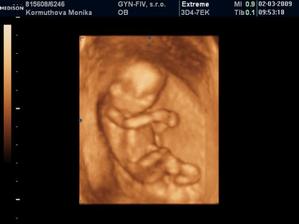

Naše 3D